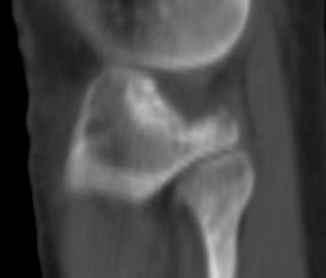

Остеосинтез при импрессионном переломе заднего отдела наружного мыщелка tibia? |

Подскажите, пожалуйста, какой выбрать доступ и способ фиксации при импрессионном переломе заднего отдела наружного мыщелка большеберцовой кости.

Женщина 40 лет, травму получила 02.01.2008, катаясь на горных лыжах.

Есть ли здесь необходимость использовать задний доступ, или можно справиться через наружный? Есть ли шансы сделать закрыто - под ЭОП через медиальное "окошко" поднять забойником суставную поврехность?

Какой лучше использовать фиксатор?